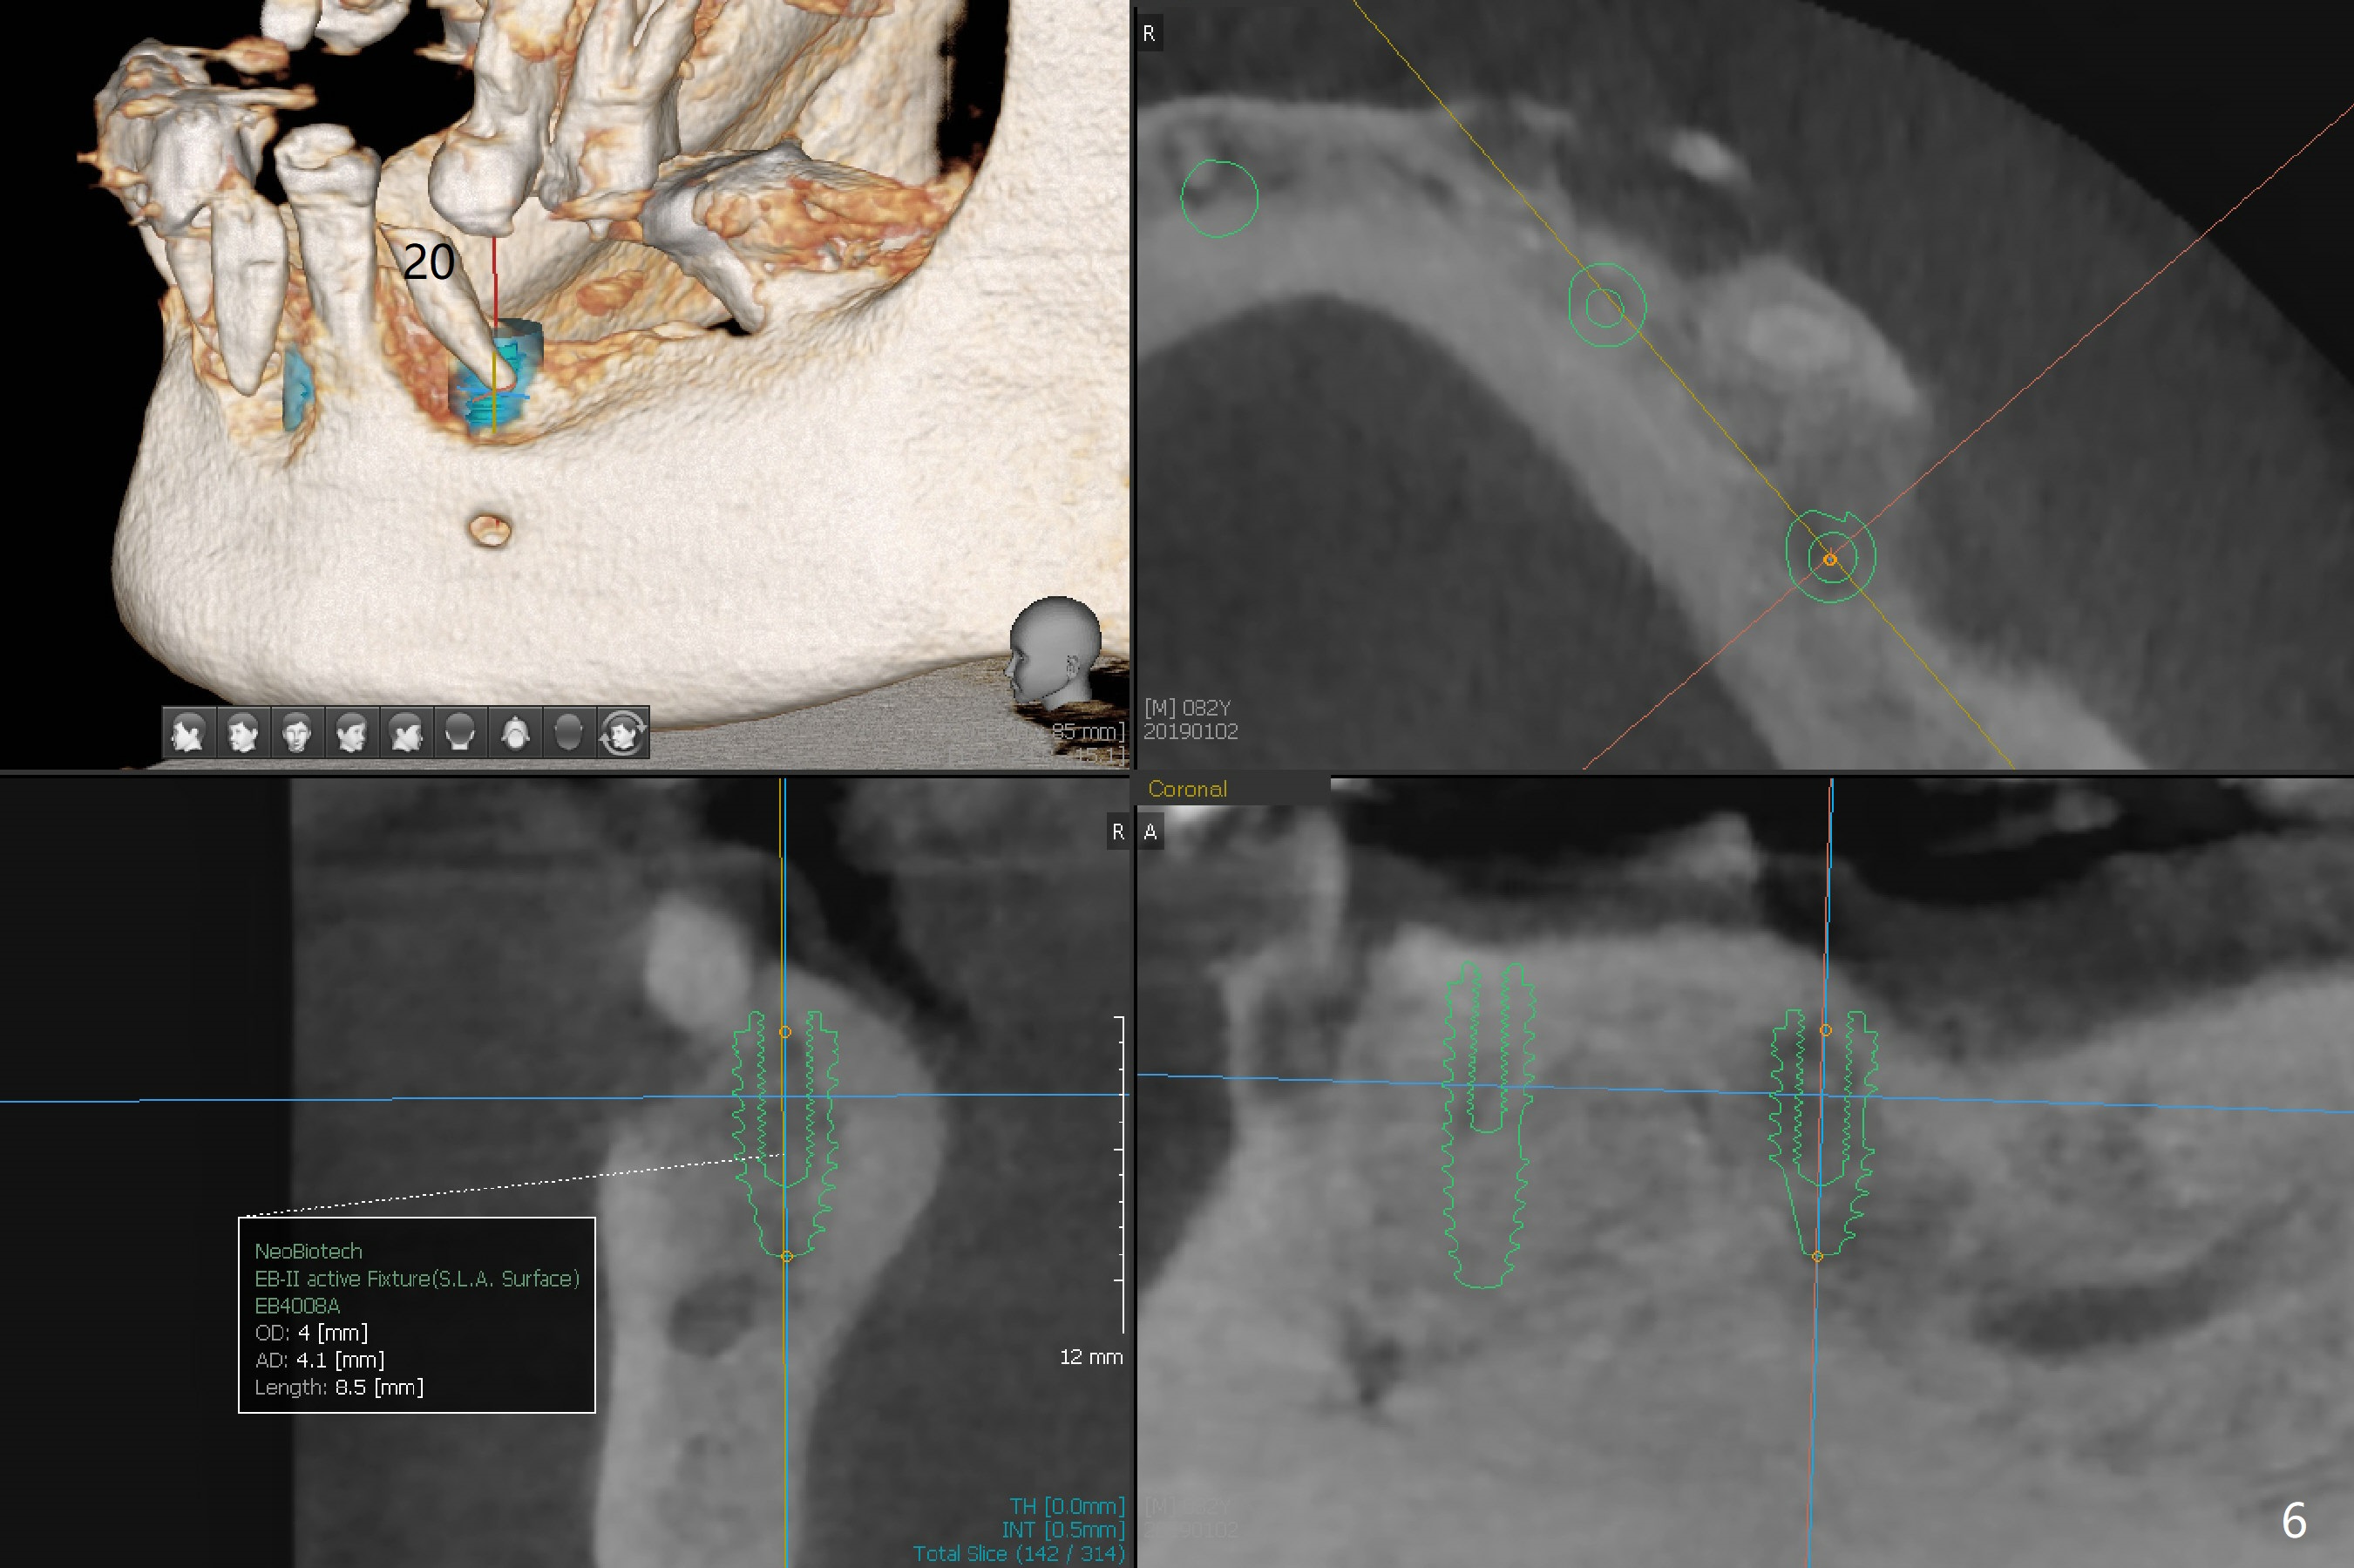

Abutments for Lower RPD

A 82-year-old man with poor dentition (upper and lower RPDs) returns to clinic for definitive treatment 2 weeks post socket preservation at #27 (with loss of the buccal plate, Fig.1). The bridge at #23-26 is mobile and to be removed. The tooth #22 appears to be restorable, but there is a buccal fistula (Fig.2 *). The root is out of the socket revealed by CBCT (Fig.5). Bone loss is severe at #20 (Fig.1,6). Three implants are going to be placed with guide at 27 or 26, 22 and 20 (Fig.3-6) with ball abutments for the lower RPD retention. Later the tooth #18 is found to be nonsalvageable.